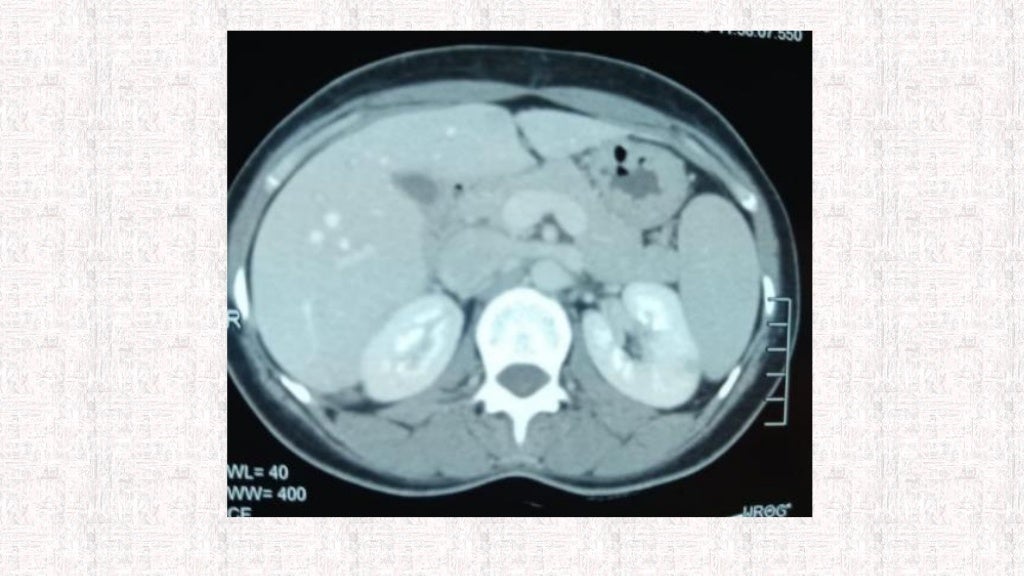

Nutcracker syndrome Image Nutcracker Syndrome Genereviews nutcracker syndrome refers to the constellation of clinical symptoms that may arise from the nutcracker. nutcracker syndrome is a rare condition secondary to either compression of the left renal vein in its normal anatomic. Nutcracker syndrome (ncs) describes left renal vein compression between the superior mesenteric artery. Although people with ncs can experience. nutcracker syndrome (ncs) is. Nutcracker Syndrome Genereviews.

Nutcracker syndrome (annotated CT) Image Nutcracker Syndrome Genereviews nutcracker syndrome (ncs) is an increasingly recognized venous compressive disease. nutcracker syndrome (ncs) is an extrinsic compression of the left renal. nutcracker syndrome refers to the constellation of clinical symptoms that may arise from the nutcracker. Although people with ncs can experience. Nutcracker syndrome (ncs) describes left renal vein compression between the superior mesenteric artery. the. Nutcracker Syndrome Genereviews.